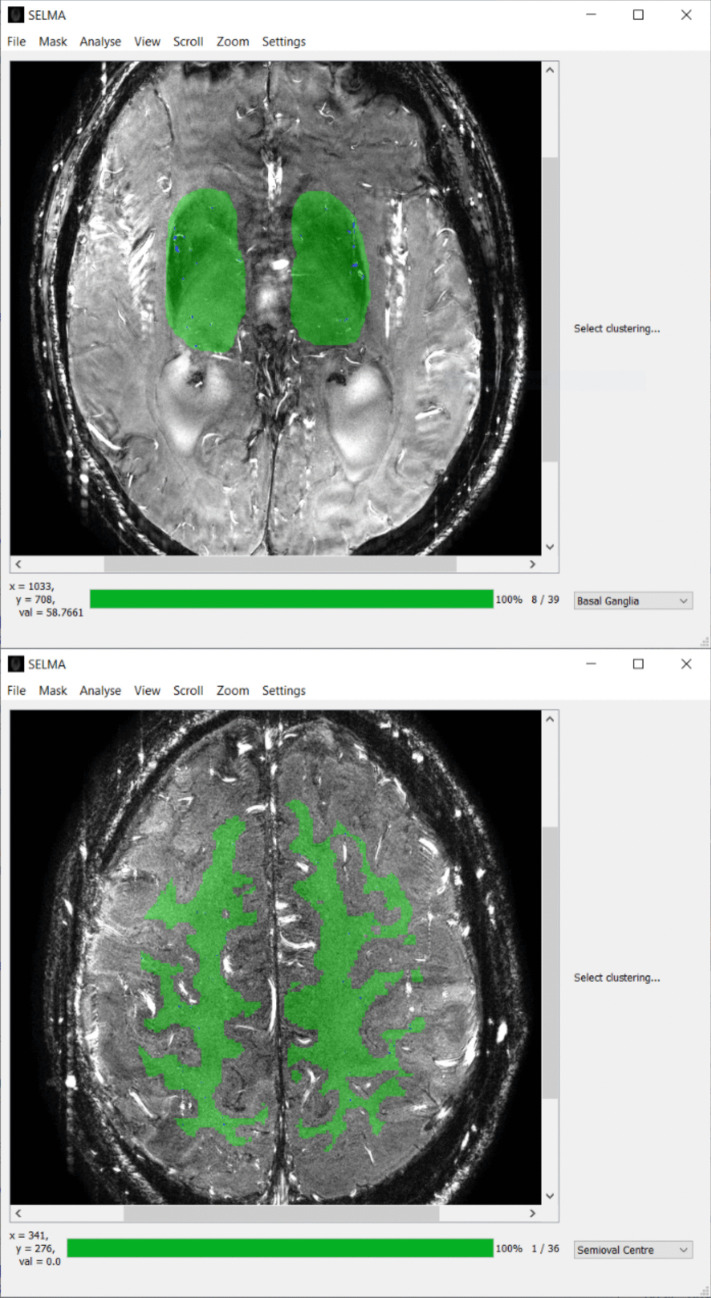

在二维平面上,通过相衬磁成像(2D PC-MRI)可以量化脑穿动脉的血流速度。速度脉搏指数(PI)可以反映这些穿孔动脉的僵硬程度,这与几种脑血管疾病有关。目前,还没有针对这些小血管的2D PC-MRI数据的开源分析工具,阻碍了这些测量的使用。在这项研究中,我们提出了小血管标记(SELMA)分析软件,作为一种新颖的、用户友好的、开源的工具,用于分析脑穿孔动脉的流速。SELMA中分析算法的实现通过Bland-Altman分析对先前发表的数据进行了验证。SELMA的评分间信度评估了来自八个不同地点的三个MRI供应商的60名参与者的PC-MRI数据。SELMA的平均速度(vmean)和速度PI与原始结果非常相似(vmean:平均差±标准差:0.1±0.8 cm/s;速度PI:平均差值±标准差:0.01±0.1),而SELMA检测到的血管数量略高(未检测到的血管数量:平均差值±标准差:4±9),这可以用SELMA的血管选择范式来解释。使用SELMA的两个操作符之间绘制的感兴趣区域的骰子相似系数为0.91(范围为0.69-0.95),Ndetected, vmean和速度PI的总体类内系数分别为0.92,0.84和0.85。结果测量在不同地点之间的差异大于供应商之间的差异,这表明在协调2D PC-MRI序列方面存在挑战,即使是在同一供应商的不同地点。我们表明SELMA是一个一致的和用户友好的小脑血管分析工具。

Blood flow velocity in the cerebral perforating arteries can be quantified in a two-dimensional plane with phase contrast magnetic imaging (2D PC-MRI). The velocity pulsatility index (PI) can inform on the stiffness of these perforating arteries, which is related to several cerebrovascular diseases. Currently, there is no open-source analysis tool for 2D PC-MRI data from these small vessels, impeding the usage of these measurements. In this study we present the Small vessEL MArker (SELMA) analysis software as a novel, user-friendly, open-source tool for velocity analysis in cerebral perforating arteries. The implementation of the analysis algorithm in SELMA was validated against previously published data with a Bland-Altman analysis. The inter-rater reliability of SELMA was assessed on PC-MRI data of sixty participants from three MRI vendors between eight different sites. The mean velocity (vmean) and velocity PI of SELMA was very similar to the original results (vmean: mean difference ± standard deviation: 0.1 ± 0.8 cm/s; velocity PI: mean difference ± standard deviation: 0.01 ± 0.1) despite the slightly higher number of detected vessels in SELMA (Ndetected: mean difference ± standard deviation: 4 ± 9 vessels), which can be explained by the vessel selection paradigm of SELMA. The Dice Similarity Coefficient of drawn regions of interest between two operators using SELMA was 0.91 (range 0.69-0.95) and the overall intra-class coefficient for Ndetected, vmean, and velocity PI were 0.92, 0.84, and 0.85, respectively. The differences in the outcome measures was higher between sites than vendors, indicating the challenges in harmonizing the 2D PC-MRI sequence even across sites with the same vendor. We show that SELMA is a consistent and user-friendly analysis tool for small cerebral vessels.